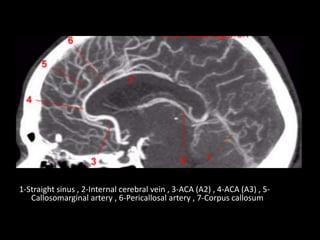

1-Straight sinus , 2-Internal cerebral vein , 3-ACA (A2) , 4-ACA (A3) , 5-

Callosomarginal artery , 6-Pericallosal artery , 7-Corpus callosum